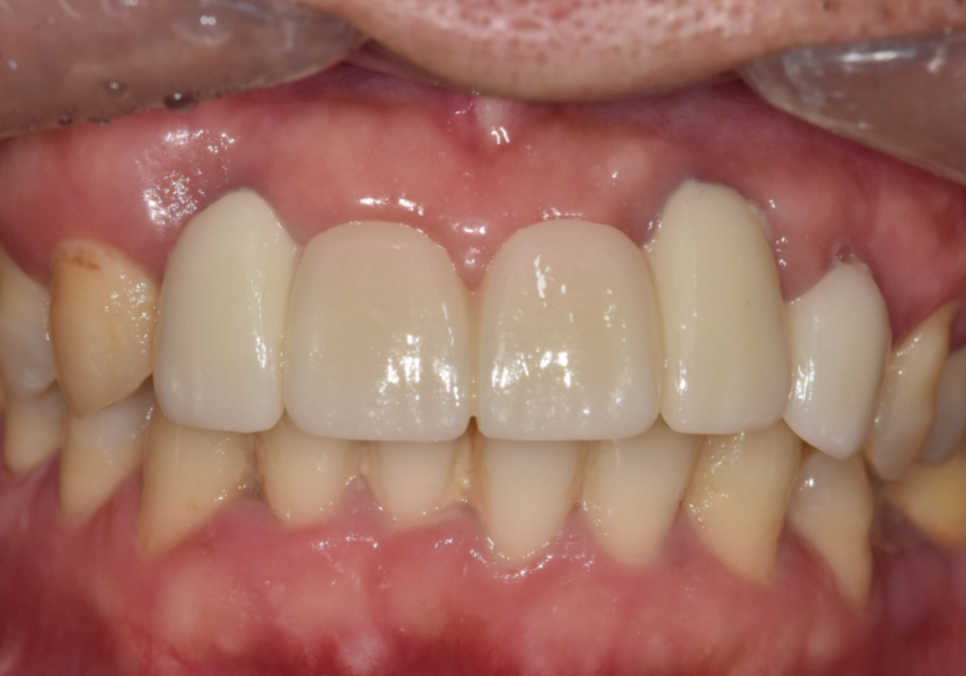

덕분에 치열이 한층 가지런해진 것은 물론이고

이전보다 입매가 안쪽으로 들어가 보여

전체적인 인상 자체가

훨씬 부드럽게 개선되었습니다.

기능적인 회복은 물론 심미적인 부분까지

자연스럽게 마무리되어,

환자분도 저도 많이 만족했던 케이스였네요^^